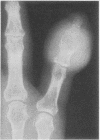

Two gouty patients developed bullae containing massive numbers of monosodium urate crystals. Both patients had had treatment with systemic corticosteroids. A burn precipitated one bulla, showing that local tissue injury can be a factor in tophus localization.